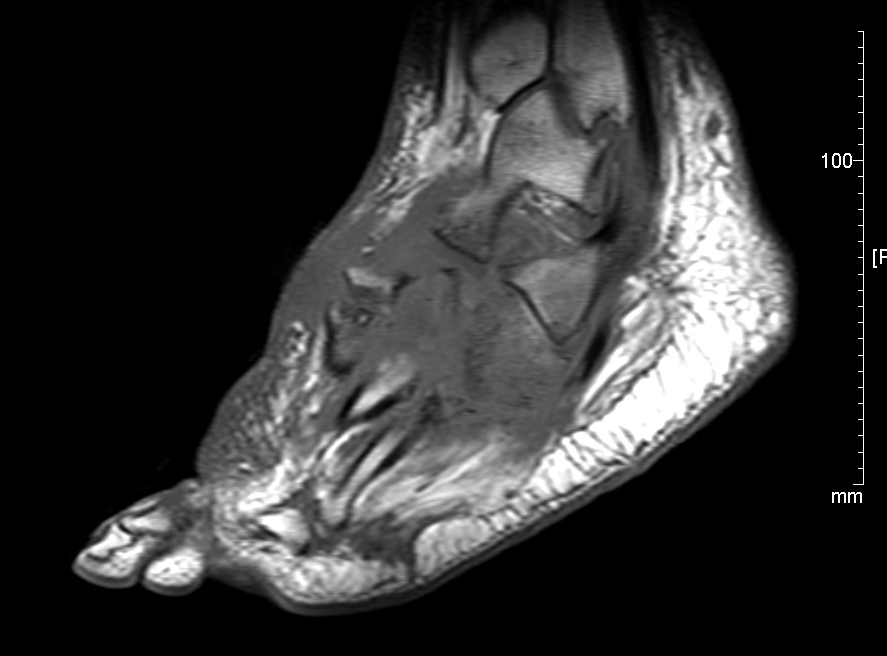

RM sin contraste para pie diabético. Las complicaciones que se pueden producir en el pie durante la evolución de la enfermedad son multifactoriales y a menudo coexisten, dificultando al clínico su diagnóstico diferencial. Un correcto diagnóstico precoz es esencial para establecer el tratamiento adecuado a cada patología.

El enfoque del estudio depende de la sospecha clínica. Cuando no se sospecha infección (osteoartropatía neuropática, artritis aséptica, fracturas) el estudio debe incluir todo el pie.

La complejidad anatómica del pie requiere una localización previa multidireccional que después permita la realización de las diferentes secuencias en los planos ortogonales al área concreta de estudio. Además, dado que son pacientes que suelen requerir de controles sucesivos es necesaria la protocolización de los estudios para que sean similares al inicial y facilitar así la valoración de la evolución de los hallazgos iniciales.

Con respecto a las secuencias a realizar, las secuencias potenciadas en T1 son necesarias para evaluar los cambios en la médula ósea y en el tejido celular subcutáneo. Las secuencias con supresión grasa (STIR) valoran el edema tanto a nivel óseo como en las partes blandas.